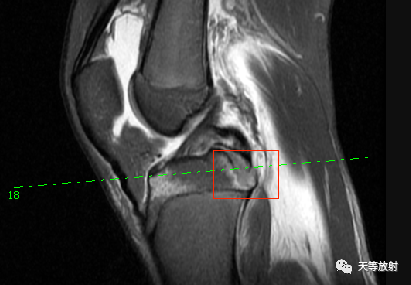

胫骨近端骨骺无分离移位,内部呈斑片状压脂高信号影并后缘撕裂性骨折,属于儿童骨骺损伤第3型。

我们再看看该患儿还存在什么问题:

上图:后交叉韧带附着点受撕裂向后方移位,同时后交叉韧带弓背向后,韧带松弛。胫骨平台后移。